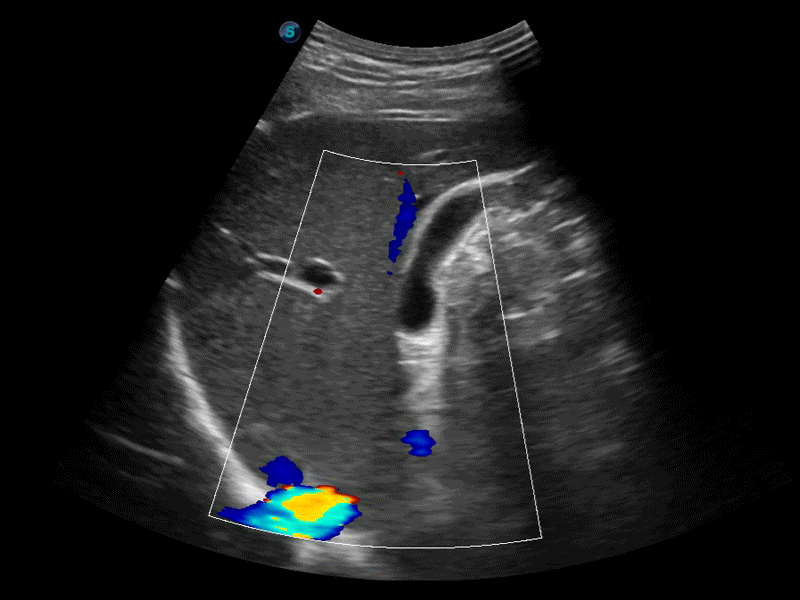

高分辨率血流成像技術(shù)提高了對(duì)低速血流信號(hào)的檢測(cè)能力。在提高空間分辨率的同時(shí),也克服了血流外溢現(xiàn)象,為用戶(hù)提供更加真實(shí)的血流動(dòng)力學(xué)信息。